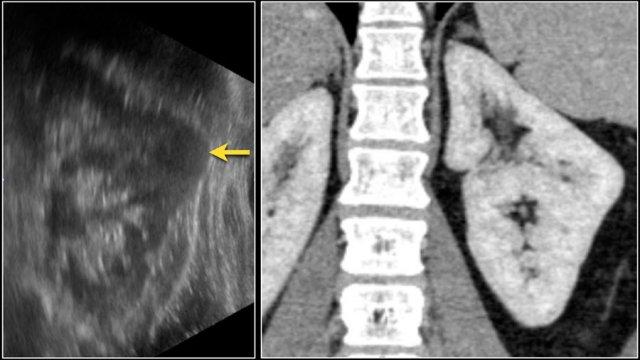

Áp xe thận thường là biến chứng của viêm bể thận cấp tính, bệnh nhân biểu hiện với nhiễm trùng đường tiết niệu, đau hông lưng và sốt.

Trên CT, áp xe thận thường biểu hiện là một tổn thương giảm tỷ trọng đồng nhất không đặc hiệu hoặc là một tổn thương dạng nang phức tạp.

Áp xe thận có thể có thành dày, không đều, ngấm thuốc kèm xâm lấn mỡ quanh thận (hình).

Ở những bệnh nhân có biểu hiện lâm sàng không điển hình, hình ảnh nang phức tạp và lan rộng vào mỡ quanh thận có thể mô phỏng ung thư biểu mô tế bào thận.

Bệnh nhân này có biểu hiện điển hình với đau hông lưng phải và các kết quả xét nghiệm phù hợp với nhiễm trùng đường tiết niệu.

Hình ảnh siêu âm cho thấy một tổn thương giảm âm với một số vùng trống âm, gợi ý thành phần chứa dịch bên trong.

Tổn thương này được xác định là áp xe.